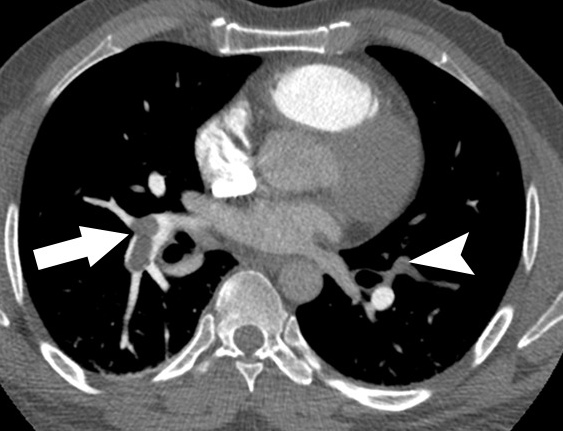

肺動脈造影CTは「足側から見上げるビュー」なので、 画像の左側=患者さんの右肺、右側=患者さんの左肺になります。

外周の白い部分は肋骨や椎体などの骨。

内部の白いのは造影剤で満たされた心臓・肺動脈。 矢印(→)部分は 本来造影されるべき肺動脈が“欠損”=血栓で詰まっている ことを示し、「肺血栓塞栓症」の診断となります。